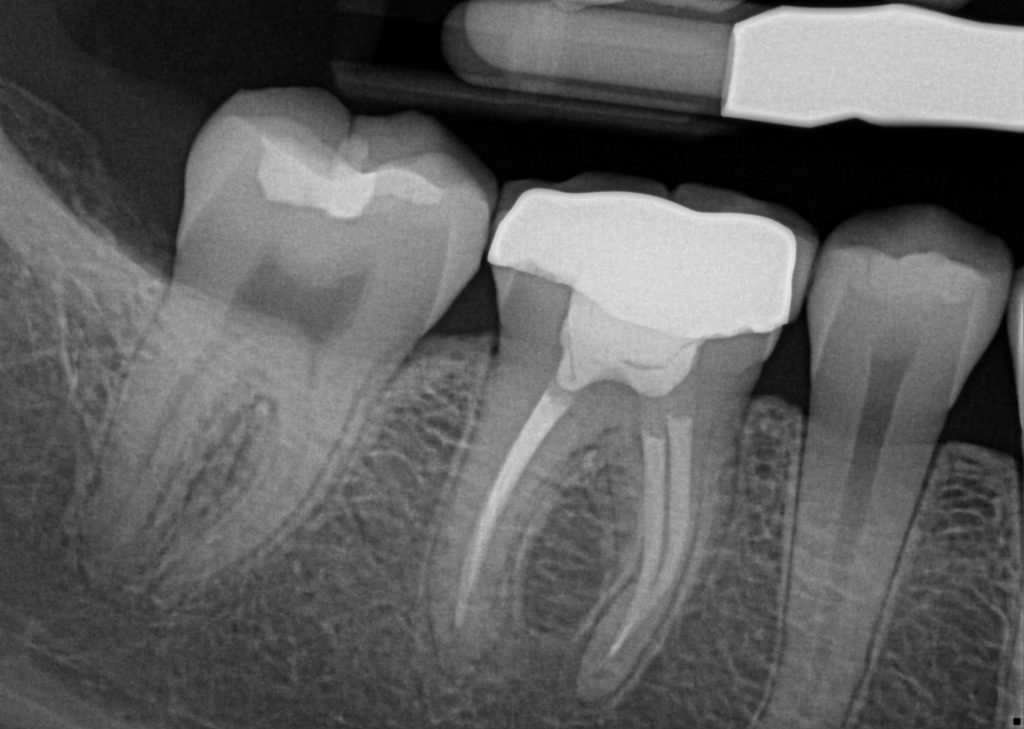

During root canal treatment, the inflamed or infected pulp is removed, and the inside of the tooth is carefully cleaned and disinfected, then filled and sealed with a rubber-like material called gutta-percha. Afterwards, the tooth is restored with a crown or filling for protection. After restoration, the tooth continues to function like any other tooth.